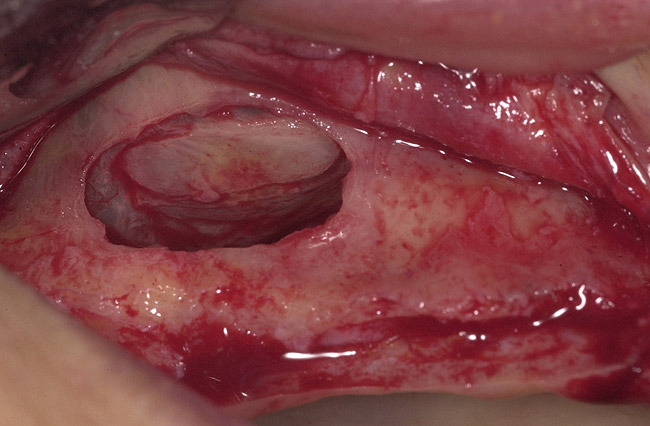

Figure 3  Buccal and radiographic views of posterior edentulism with significant sinus pneumatization in the molar region.

Figure 3

Figure 4  Lateral wall osteotomy.

Figure 4

The elevated membrane leaves an empty space in the lower third of the sinus that will be augmented with the bone graft. Then, a collagen membrane is used to cover the window, and the flaps are sutured passively to obtain primary closure. A healing period of approximately 6 months is recommended for initial bone maturation (Figure 1, Figure 2, Figure 3, Figure 4, Figure 5, Figure 6, Figure 7, Figure 8 and Figure 9).